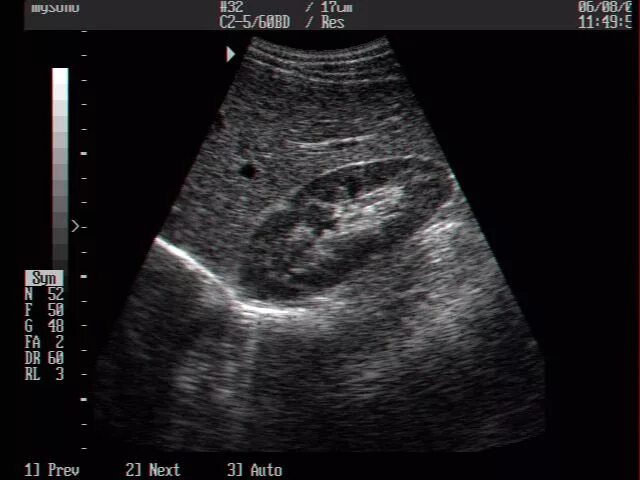

Узи сердца узи почек